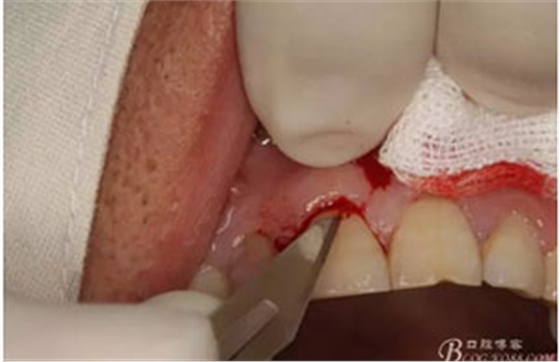

圖6.行唇側(cè)角形切口(11近中垂直切口+齦溝內(nèi)水平切口)垂直切口距離前庭溝約1~2mm。這樣可以減輕術(shù)后腫脹。

圖7. 角形切口中的齦溝內(nèi)切口情況:11號刀片伸進齦溝內(nèi)斜切。